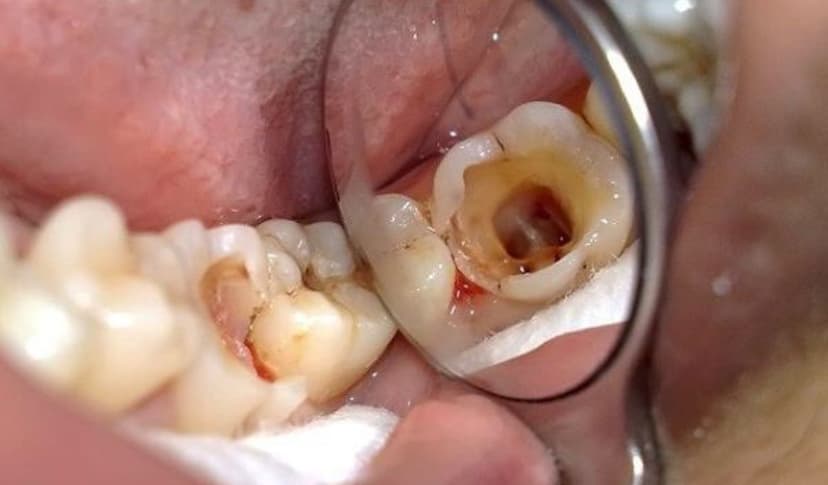

2.2. Răng có những vết đen hoặc xuất hiện lỗ li ti

Sâu răng ban đầu thường biểu hiện bằng các đốm trắng mờ, sau đó chuyển sang màu nâu hoặc đen. Một số trẻ còn xuất hiện lỗ nhỏ trên bề mặt răng hàm – đây là dấu hiệu men răng đã bị phá hủy, cần đưa trẻ đi khám nha sĩ ngay để tránh tình trạng sâu răng tiến triển.

– Sâu răng nặng: Lúc này, vi khuẩn đã xâm nhập vào tủy răng, gây đau nhức dữ dội. Bác sĩ có thể chỉ định điều trị tủy răng sữa, giúp loại bỏ phần tủy bị viêm và giữ lại chân răng để răng vẫn duy trì chức năng. Nếu răng bị hư hỏng quá nặng, không thể bảo tồn, trẻ có thể cần nhổ răng. Sau nhổ, bác sĩ sẽ tư vấn giải pháp phục hình phù hợp để đảm bảo răng vĩnh viễn mọc đúng vị trí sau này.